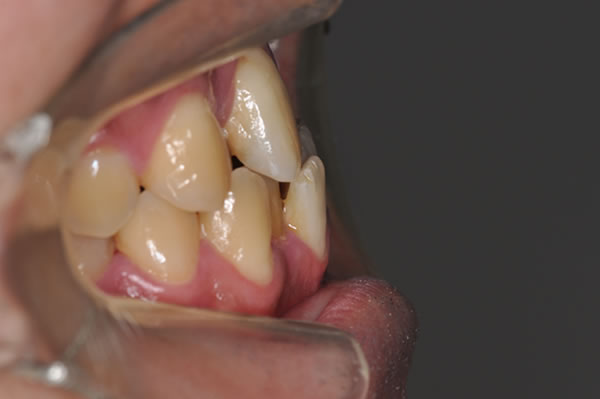

反対咬合症例

治療後